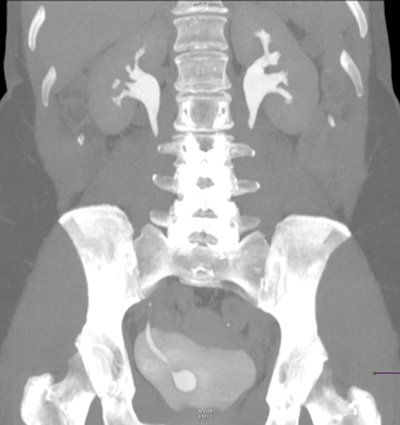

Case 4

Right sided ureterocoele, with a normal upper tract.

Simple (intravesical) 25% or ectopic 75%.

Majority of ectopic ureterocoeles are associated with a duplex collecting system.